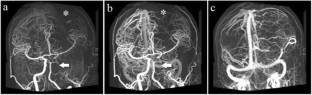

Fig. 2